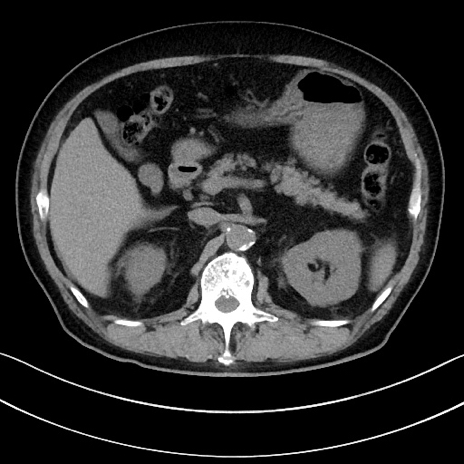

症例15(横断像)

冠状断像

【症例】70歳代男性

【主訴】腹痛

【現病歴】今朝から腹痛あり。全体的に痛い。特に左上の方。排ガスが今日はない。冷や汗が出る。

【既往歴】直腸癌術後

【身体所見】左側腹部〜上腹部に圧痛あり。腹膜刺激症状明らかなではない。軽度反跳痛。左下腹部に術後瘢痕あり。

【データ】WBC 7700、CRP 0.02